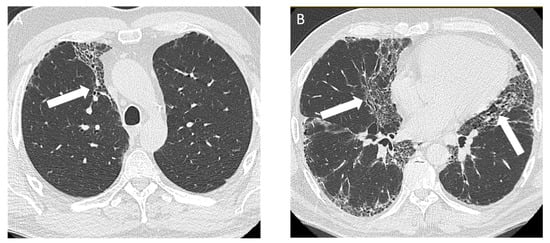

Figure 1.

A 45-year-old non-smoking male, previously a stone mason and countertop stone cutter, diagnosed with complicated silicosis and progressive massive fibrosis. (A) Axial computed tomography image shows conglomerate bilateral upper zone masses with associated architectural distortion consistent with progressive massive fibrosis (white arrows); (B) coronal image demonstrates the upper lung zone predominance; (C) chest radiograph demonstrates profuse small circumscribed pulmonary nodules with an upper lung zone predominance.